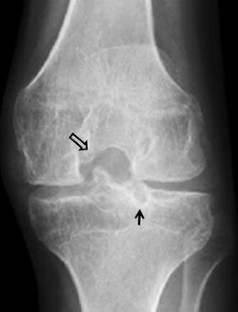

Fig. 4